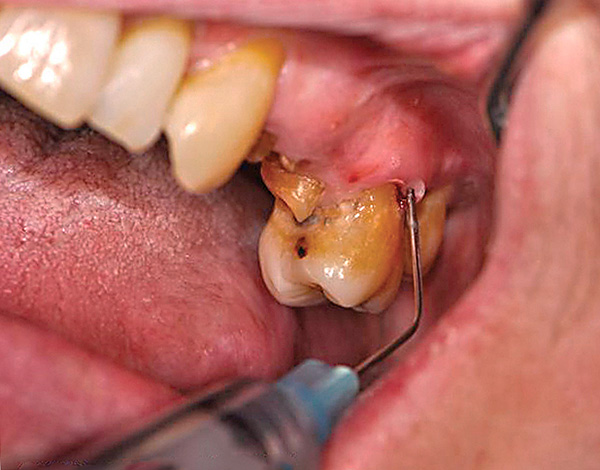

A foto abaixo mostra um exemplo de um dente da frente quebrado a ser removido: